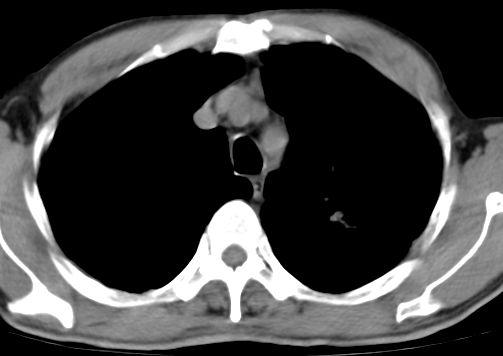

标题: CT10147:男、55岁,咯血10天,有结核病史。 [打印本页]

标题: CT10147:男、55岁,咯血10天,有结核病史。

支持,另纵隔淋巴结肿大

左上肺见软组织密度肿块影,边缘呈分叶状,可见毛刺,肺门纵隔淋巴结增大,考虑左侧周围型肺癌。左上肺陈旧性结核纤并维化。

左上周围型肺癌;伴纵膈淋巴结转移。

左上肺尖后段上面陈旧性结核,下面邻近左肺门旁可见软组织肿块影,与上肺v关系密切,左肺门及气管隆突下可见增大的淋巴结影,考虑1.左上肺ca(周围型)伴肺门纵隔内淋巴转移 2.左上肺陈旧性tb

左肺中心性肺癌并纵隔及肺门淋巴结转移

左肺上叶中心性肺癌,伴肺门及纵隔淋巴结肿大